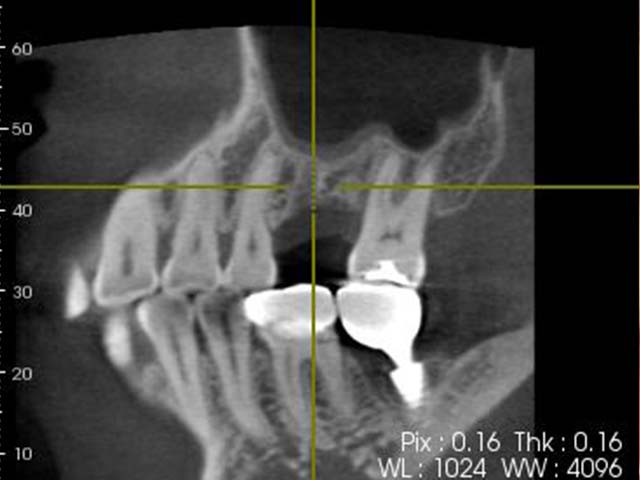

人工植牙 首頁 案例分享 人工植牙 前牙植牙 更多 牙橋嚴重蛀牙,即拔即種,避免二次傷口 更多 齒槽骨保存術+植牙 更多 前牙審美植牙 更多 微創植牙 更多 小臼齒植牙 更多 即拔即種 更多 鼻竇增高術(垂直)+植牙 更多 鼻竇增高術(側窗) 更多 «1»